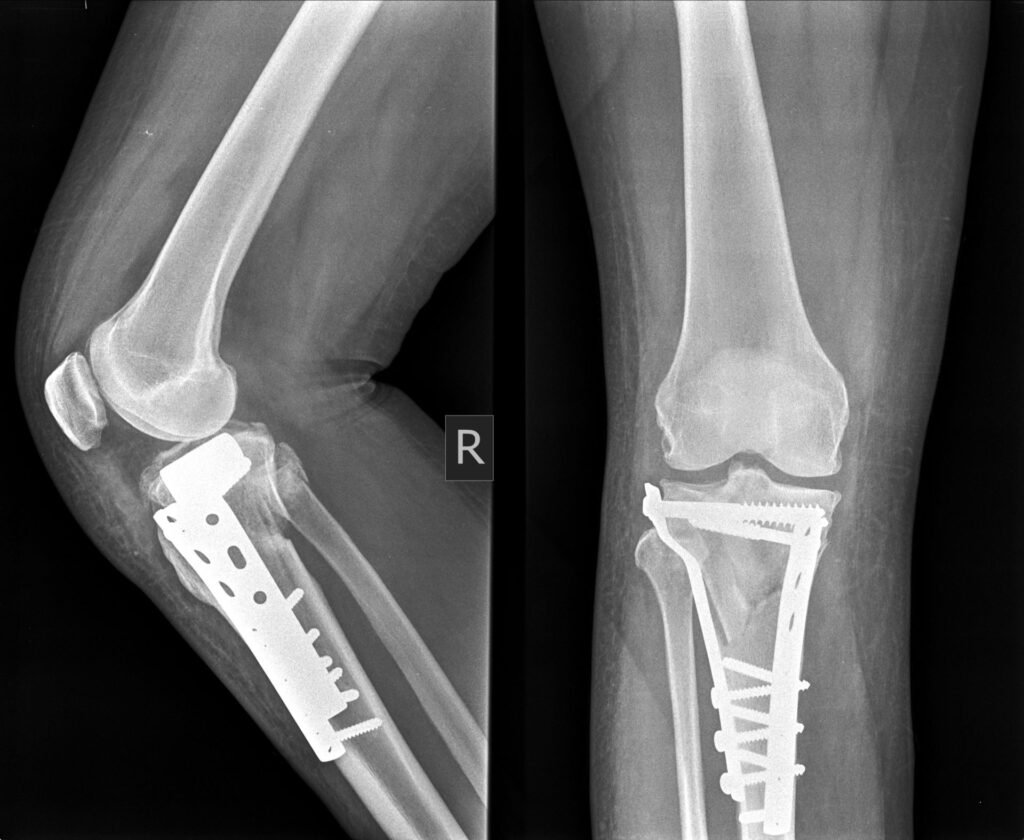

Internal Fixation Surgery (Plates, Screws & Rods)

Internal Fixation Surgery in Indore involves placing metal plates, screws, or rods inside the body to hold the fractured bone securely. These implants are designed to support healing while allowing gradual movement.

This method is commonly used for long bones, joint fractures, and complex injuries where precise alignment is essential